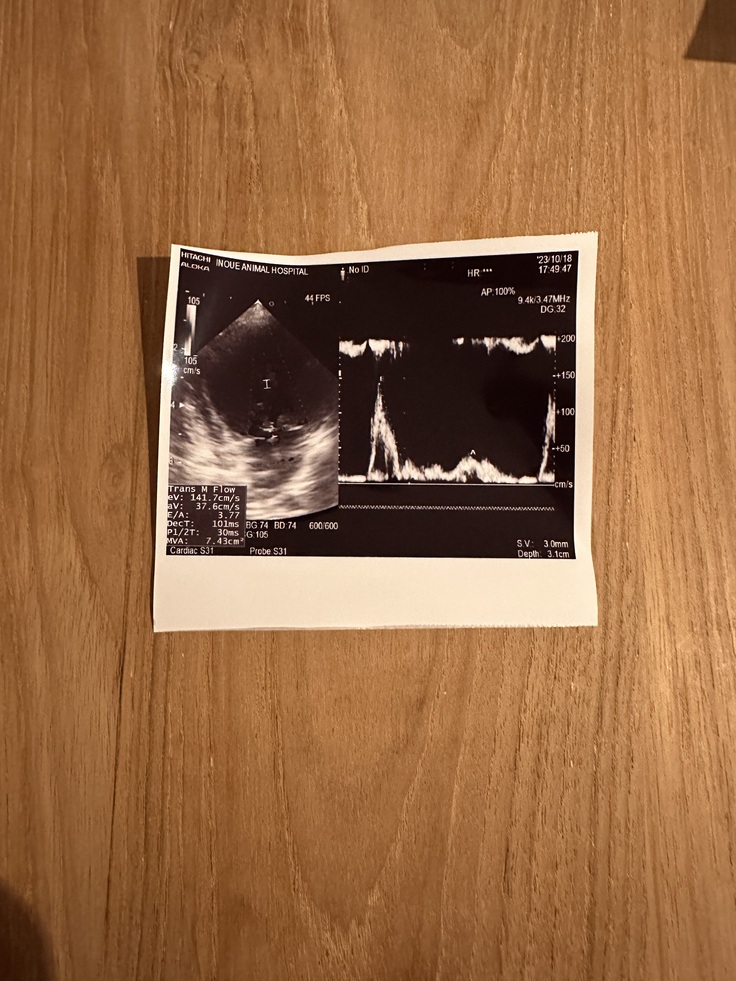

かかりつけの病院に行ってきました!

今日は、ららの定期検診で腎臓と心臓のチェックをしてもらいました!

結果は、腎臓の数値が前回より悪くなっているとのことでした><(前回の検査結果は横ばいでした)

利尿剤の薬を前回少なくしてもらったのですが、それの影響はあるかもしれないと!!!

薬のバランスで循環が良くなったり悪くなったりするとのこと、前回ららの腎臓のことを考えて薬をへらしたのですが、ららの場合少なくしたことによって循環が悪くなり検査結果が悪くなったのではないかとのことで、薬の量は元に戻すことにしました!!!